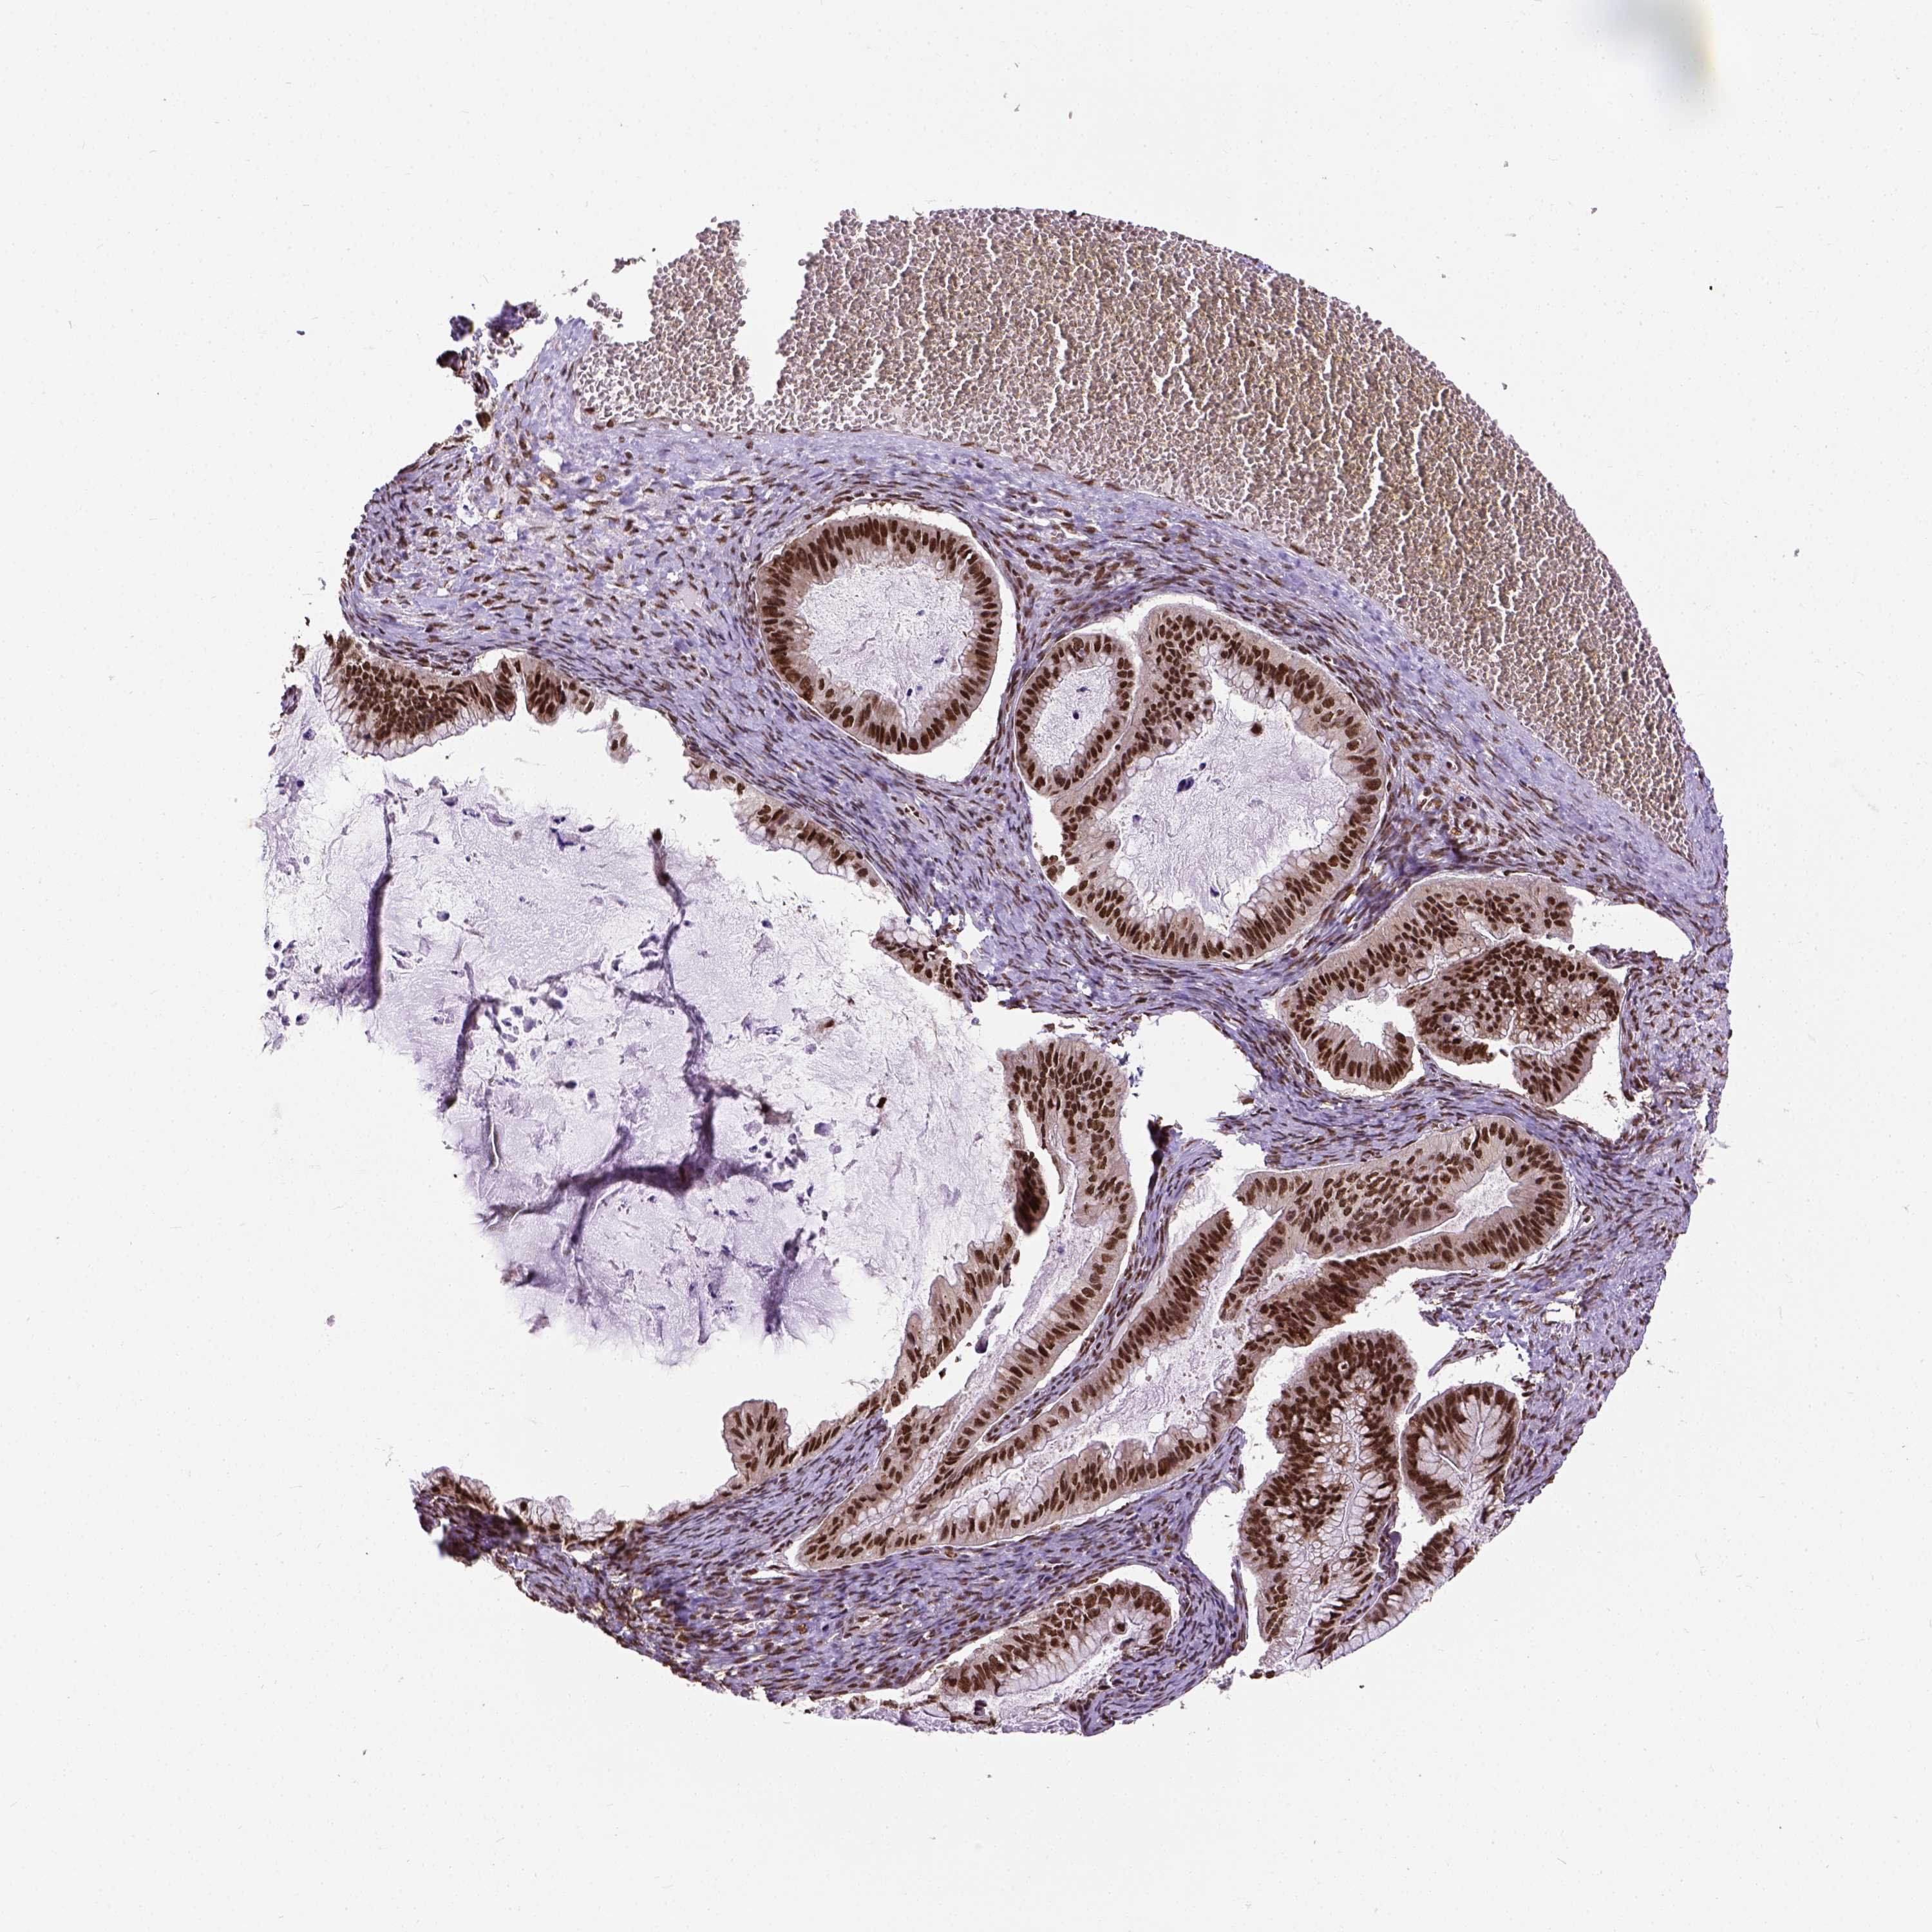

OVARIAN CANCER - Protein expressioni

A mouse-over function shows sample information and annotation data. Click on an image to view it in a full screen mode. Samples can be filtered based on level of antibody staining by selecting one or several of the following categories: high, medium, low and not detected. The assay and annotation is described here.

Note that samples used for immunohistochemistry by the Human Protein Atlas do not correspond to samples in the TCGA dataset.

Antibody stainingi

Antibody staining in the annotated cell types in the current human tissue is reported as not detected, low, medium, or high, based on conventional immunohistochemistry profiling in selected tissues. This score is based on the combination of the staining intensity and fraction of stained cells.

Each image is clickable and will lead to virtual microscopy that enables deeper exploration of all samples and also displays staining intensity scores, fraction scores and subcellular localization as well as patient and tissue information for each sample.

Antibody HPA021238

Antibody HPA062245

Antibody CAB069927

Staining

High

Medium

Low

Not detected

Intensity

Strong

Moderate

Weak

Negative

Quantity

>75%

75%-25%

<25%

None

Location

Nuclear

Cytoplasmic/membranous

Cytoplasmic/membranous,nuclear

Cystadenocarcinoma, serous, NOS

Cystadenocarcinoma, mucinous, NOS

Carcinoma, endometroid